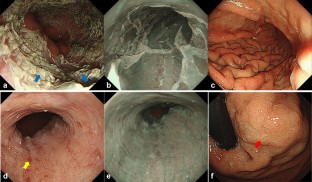

Fig. 2